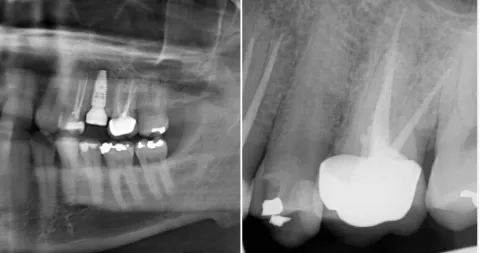

I bloggen hittar du artiklar om de senaste framstegen inom tandimplantat, inklusive tekniker som möjliggör direktinstallation av implantat i samband med tandutdragning, användning av tillväxtfaktorer som PRF och PRP för snabbare läkning samt hur modern bilddiagnostik och kirurgiska guider bidrar till ökad precision och kortare behandlingstid. Vi berättar också om hur vi arbetar med avancerade lösningar som benaugmentation, sinuslyft och UV-aktivering av implantatytor med Plasmaprep™ för att optimera resultatet.

Direktimplantat i överkäken – tandimplantat direkt efter utdragning

sinuslyft tandimplantat

För lite ben för implantat i överkäken? Sinuslyft är en säker metod för att skapa...